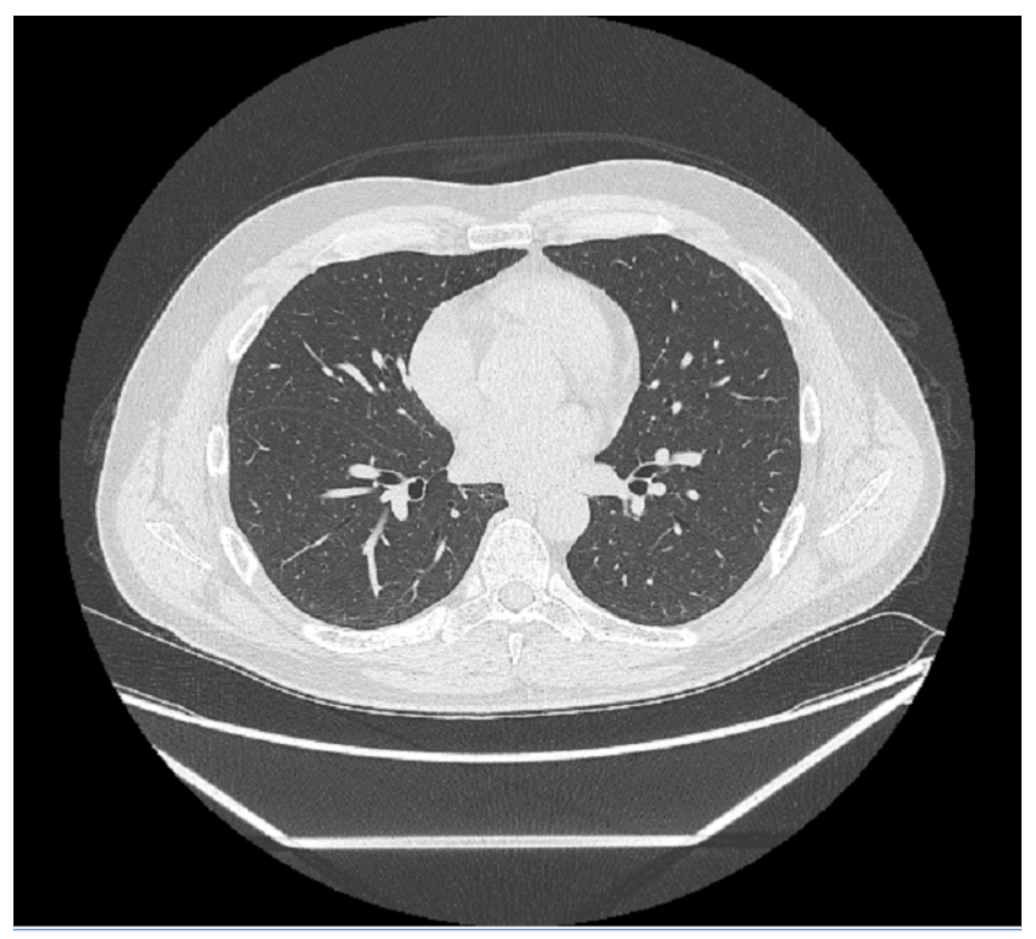

Every medical image is a combination of grey-levels that produce the morphology of the image. In this specific case, the attention is focused on HRCT images of the lung. In particular, the external part of a healthy lung would be white, while the inner part of the lung would be black. In this black part there could be different movements that display normal respiration and the performance of vital functions. Through these images, in the black section of the lung, radiologists can note some white spots that can be marked as disease symptoms, but they would not know to which disease the marks refer. For example, in Figure 5, Figure 6 and Figure 7 there are three different HRCT belonging to three different patients: one image has ”very black” lungs, while the others have some white spots. As a matter of fact, the Figure 5 is an HRCT of a healthy patient and it does not show white spots or pneumonia signs. The Figure 6 and Figure 7 are similar, because they both show some disease marks: the first is from a COVID-19 patient, while the second is from a lung disease patient. Thanks to this, it is clear just how difficult it is to see the differences between a general pneumonia and Coronavirus disease with the naked eye.

Figure 5. HRCT scan of a healthy patient. The image shows an example of healthy lung parenchyma.